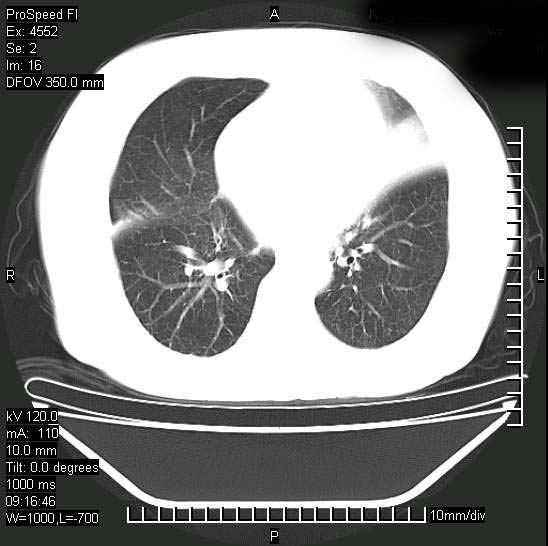

标题: CT15528:女性,79岁,近几日晚上高热,39度,仍咳少量血 [打印本页]

十几年前曾患肺结核,一周前突咳血约100ml,中性粒细胞稍高,诊断两上肺陈旧结核,下肺炎症,给予抗炎治疗,近几日晚上高热,39度,仍咳少量血,4天前ct及今天ct上传。

今天ct

短短几天内,病变范围明显增多扩大,以左侧明显,而且双侧出现胸水,还是考虑感染.

短短几天内,病变范围明显增多扩大,以左侧明显,而且双侧出现胸水,我更多考虑左侧中心性肺癌并并阻塞性不张及肺炎,炎症变化也太快了!

无论是肿瘤还是炎症4天的时间都发展够快的,并且还在治疗中,如果说是左肺癌那么右肺的病变不好解释,本人更加倾向于炎症,左肺舌叶支气管被痰栓或血凝块堵塞,造成阻塞性肺炎。

1)两肺结核并感染。2)不排除左肺上叶中央型肺癌并阻塞性肺炎、肺不张可能;建议行纤支镜检查。3)右肺门及纵隔淋巴结肿大。4)双侧胸腔积液。

陈旧性肺结核及左下肺不张,咯血后肺部感染,双胸腔积液,高热可能与痰液引流不畅有关。